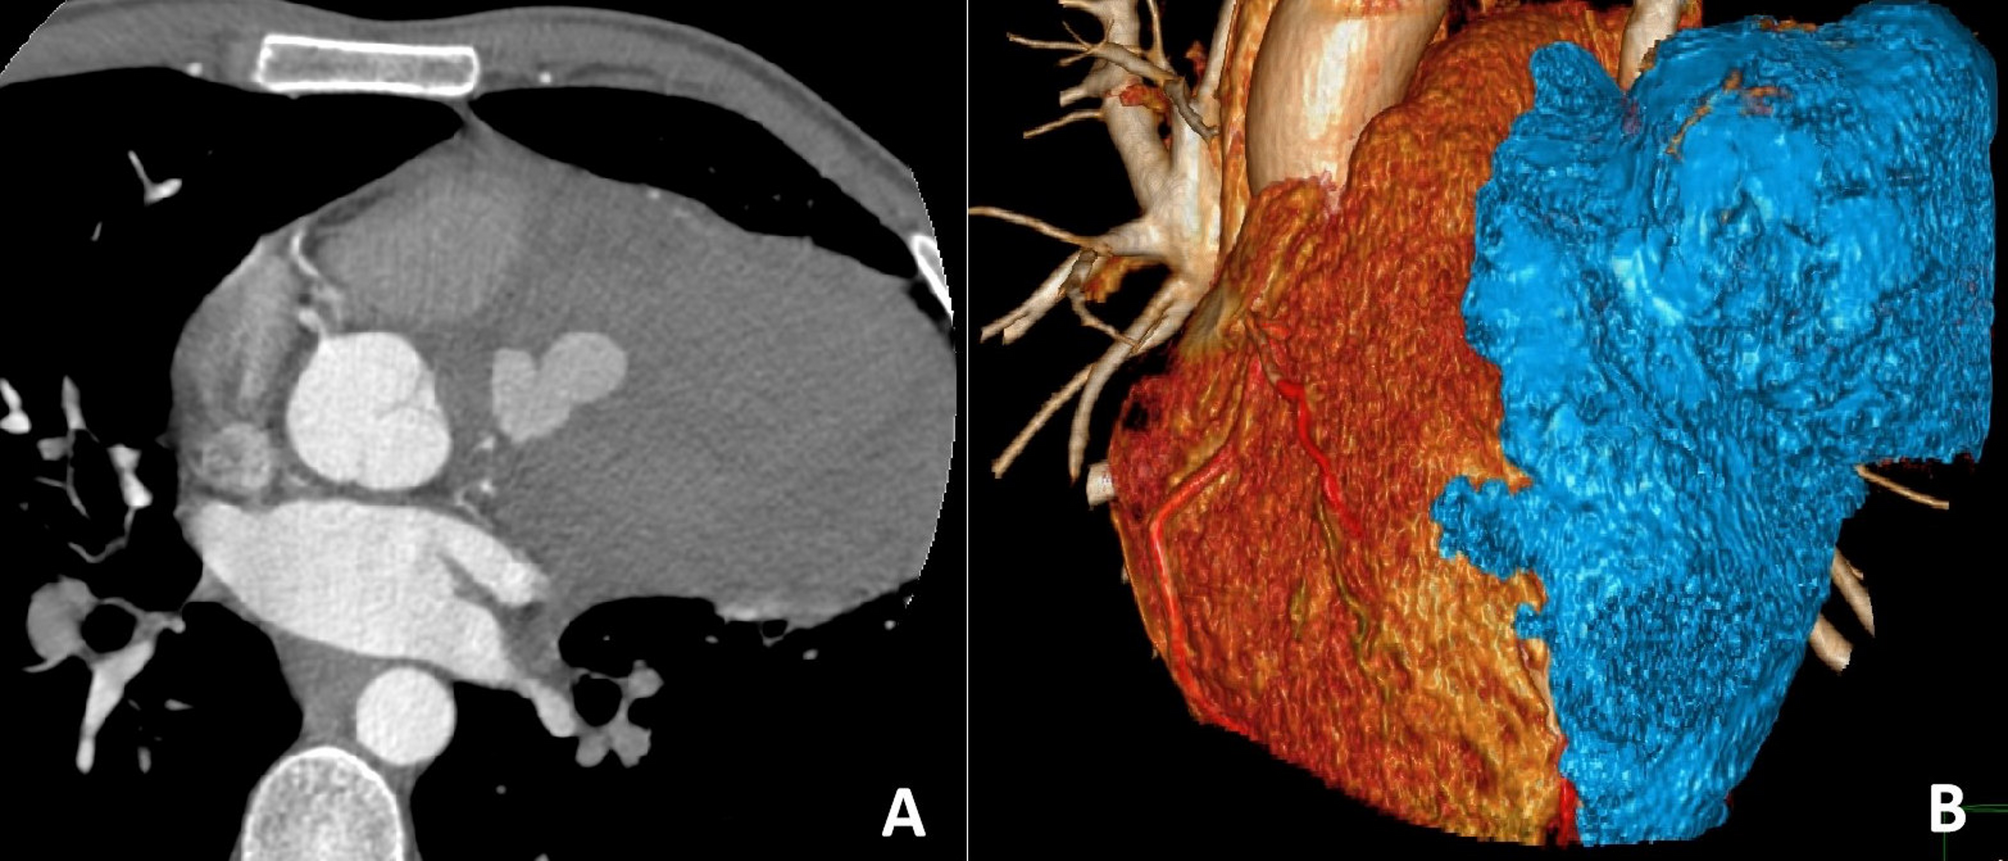

Man in his third decade with a giant coronary artery aneurysm | Journal of Cardiothoracic Surgery

A 27-year-old male presented with a 4-month history of intermittent retrosternal chest pain described as dull and exertion-exacerbated, accompanied by 3-day hemoptysis. He had no prior vascular risk factors, family history of…